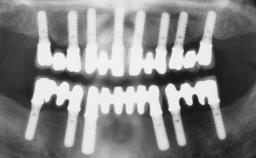

Conventional Loading of Six Implants in the Mandible and Final Restoration with a Full-Arch Metal-Ceramic FDP

# of Implants 6

Defining Characteristics Fully edentulous lower jaw to be rehabilitated with two or more implants

Modality > 4 implants, extending to mental nerve region

Bone Volume Horizontally and vertically sufficient